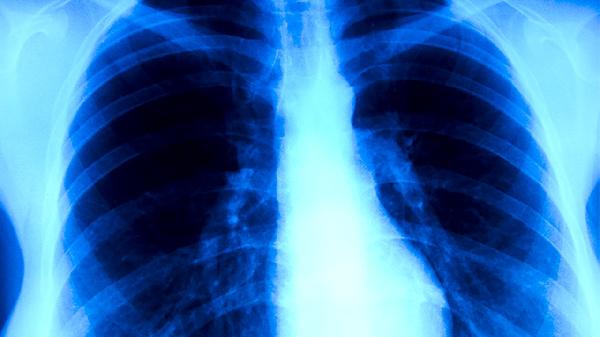

肺結(jié)核不存在良性或惡性的醫(yī)學(xué)分類,所有類型的肺結(jié)核都具有傳染性。肺結(jié)核的傳染性主要與患者是否排菌有關(guān),痰液中能夠檢出結(jié)核分枝桿菌的開放性肺結(jié)核患者是主要傳染源。

處于活動(dòng)期的肺結(jié)核患者,特別是痰涂片檢查結(jié)果為陽性的情況,傳染性較強(qiáng)。結(jié)核分枝桿菌會隨著患者咳嗽、打噴嚏或大聲說話時(shí)產(chǎn)生的飛沫核傳播到空氣中。當(dāng)健康人吸入這些含有細(xì)菌的微小飛沫,細(xì)菌進(jìn)入肺泡就可能引發(fā)感染。這類患者需要進(jìn)行規(guī)范的抗結(jié)核治療,在治療初期尤其需要注意隔離防護(hù),直到痰菌檢查轉(zhuǎn)為陰性,傳染性才會顯著降低。

部分肺結(jié)核患者,例如病灶已經(jīng)鈣化或纖維化的陳舊性肺結(jié)核,或者經(jīng)過有效抗結(jié)核治療、痰菌持續(xù)陰性的患者,其傳染性極低,甚至沒有傳染性。痰涂片和培養(yǎng)檢查未發(fā)現(xiàn)結(jié)核菌的患者,通常被認(rèn)為不具有傳染他人的能力。一些非活動(dòng)性肺結(jié)核或結(jié)核性胸膜炎患者,由于病原菌并未通過呼吸道排出,也不構(gòu)成傳染風(fēng)險(xiǎn)。

與肺結(jié)核患者共同生活或密切接觸時(shí),應(yīng)注意保持室內(nèi)通風(fēng)良好,患者應(yīng)佩戴口罩并養(yǎng)成良好的衛(wèi)生習(xí)慣,如咳嗽時(shí)遮掩口鼻。接觸者自身也應(yīng)增強(qiáng)免疫力,一旦出現(xiàn)長期咳嗽、午后低熱、盜汗等癥狀,須及時(shí)進(jìn)行結(jié)核病篩查。肺結(jié)核的治療遵循早期、聯(lián)合、規(guī)律、全程、適量的原則,患者應(yīng)嚴(yán)格遵從醫(yī)囑完成整個(gè)療程,這是治愈疾病并消除傳染性的關(guān)鍵。